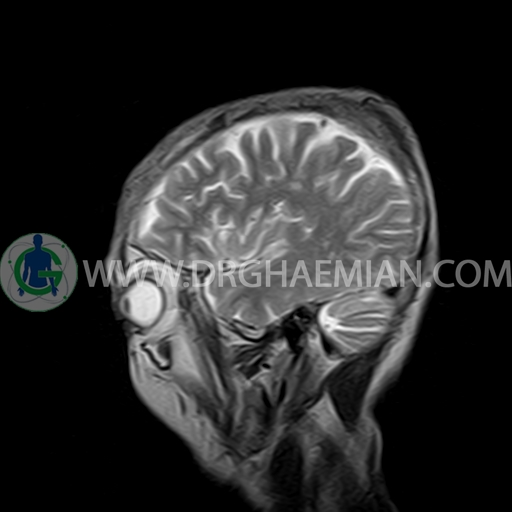

ام آر آی مغز با استفاده آهنربا های قوی و امواج رادیویی تصاویری از مغز و بافت های عصبی پیرامونی آن ایجاد می کند. در این کیس مننژیوم به همراه هیپراستوز استخوانی سمت چپ دیده می شود.

BRAIN MRI

(Without contrast)

Technique:Axial FLAIR, Axial, sagittal, FSE T2, coronal T1 .

a well – defined dural based mass lesion ( 27x55mm ) in left parietal region with signal change in adajacent bone suggestive for meningioma with bone hyperosteosis

mass effect & edema in left parietal lobe

are seen

COMMENT : MRI with contrast is recommended .